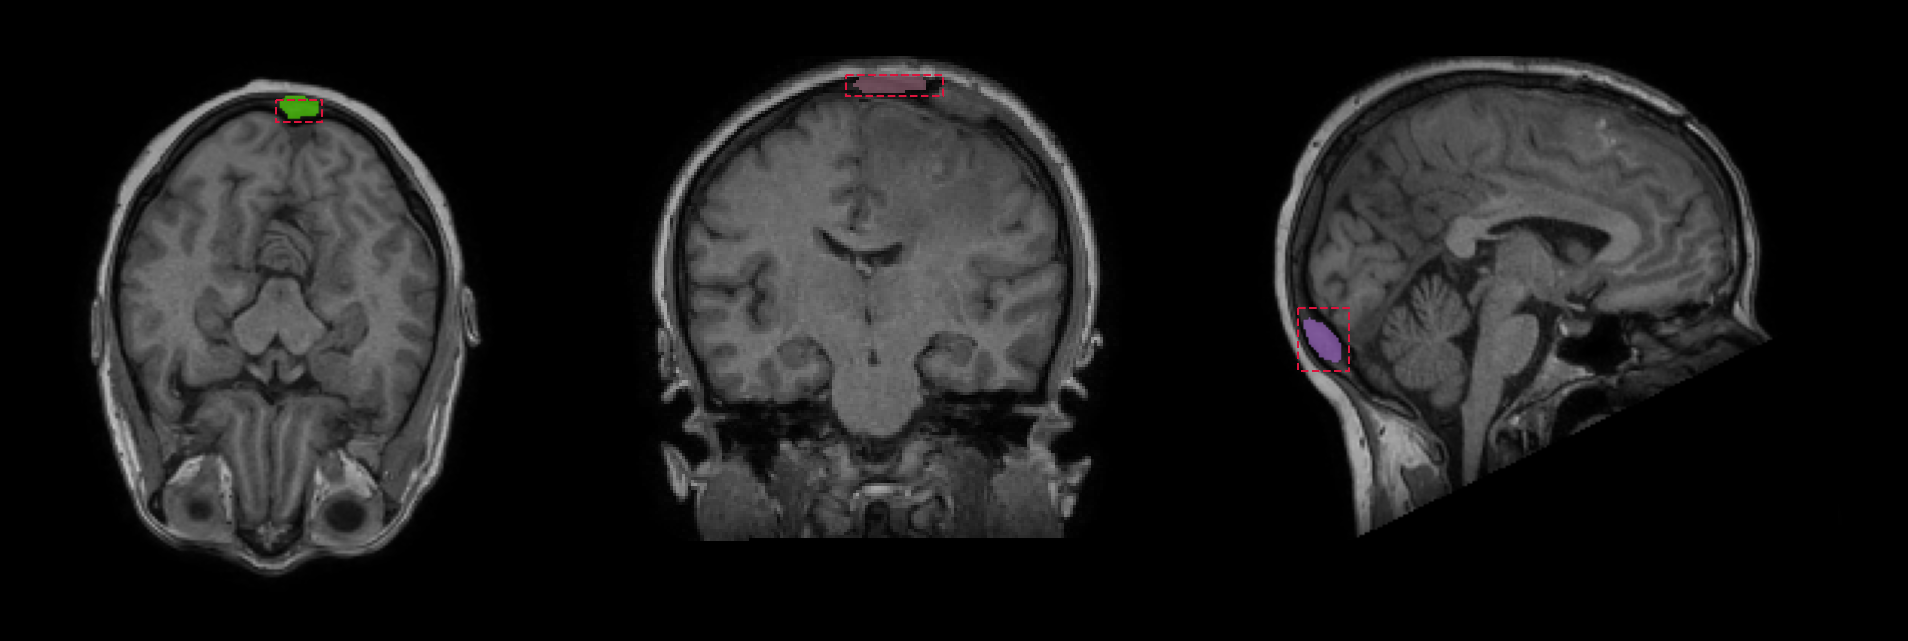

Refer to caption

(a) Bounding box approach

(b) Point prompt approach

Figure 4: Results of skull segmentation from MR images with the use of MedSAM: (4(a)) bounding box and (4(b)) point prompt approaches. Bounding box approach failure stems from a fact that segmented skull structure is not propagated through the whole image, and only small parts are captured. For point prompt, the model is unable to identify the skull and propagates segmentation into brain.

Quantitative analysis of the CUT method shows that it can provide better results in terms of DSC and SDSC than the combination of skull stripping with subtraction and masking as shown in Table 1. Importantly, we find out that MedSAM [21] struggles with the skull segmentation in MR images and fails to propagate the segmentation mask in both bounding-box and point-prompt (experimental) approaches. This can be potentially solved via task-specific fine-tuning (as the authors mention this MedSAM capability in their work). Good results of our method suggest that it is a promising direction for designing a fully unsupervised framework of skull segmentation from MR images, that can be used for downstream tasks (such as defect segmentation), and with the use of super-resolution LapSRN module, the requirement of high-resolution CT images for tasks like craniectomy or surgery planning is also met. What’s more, both CUT and LapSRN are relatively simple in terms of architectural design and also their learning objectives, hence they can be adapted to other translation tasks, or fine-tuned for other anatomical structures. With CUT we were able to obtain good generalization capabilities due to the very high diversity of the used dataset. Importantly, we also note several limitations of our methodology and leave it as a potential direction for further work. First of all, produced results sometimes include some blurriness; this can be attributed to using convolutional networks with a relatively small number of filters and a shallow network depth. This issue stems from the challenges of designing large networks for high-resolution volumetric data. Even the latest GPUs struggle with VRAM capacities when trying to fit large tensors and extensive 3-D networks. Secondly, while DSC results are better than other methods, they still require improvement to meet the demands of potential real-world medical applications. Finally, the primary motivation of this work was to achieve generalization capabilities for the segmentation task in an unsupervised and unpaired manner. Therefore, we do not compare our results with other methods used in MR-to-CT translation, as these are not primarily focused on segmentation. Nevertheless, we acknowledge that some existing translation methods may be more effective than CUT, and other super-resolution modules could outperform LapSRN. We consider this a potential area for further improvement, research, and investigation.